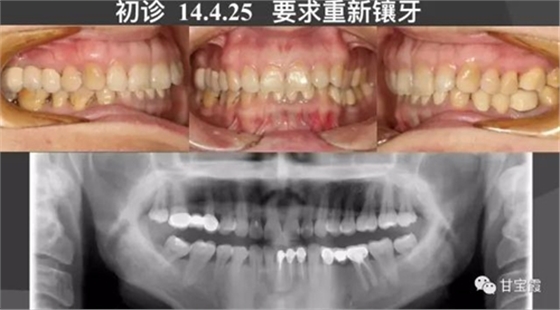

一位33歲女性患者,由朋友介紹來(lái)我診所鑲牙,初診檢查發(fā)現(xiàn)她牙弓形態(tài)不好看,還缺兩顆牙,幾年前曾經(jīng)鑲過(guò)九顆烤瓷牙,如下圖所示,如今口腔有異味,要求重新鑲牙。

大家都知道以前缺一顆牙要鑲?cè)w烤瓷牙,缺兩顆要鑲六顆烤瓷牙,因而好好的一顆牙就因?yàn)殍偲渌辣荒サ袅艘粚?,十分可惜。這次就診根據(jù)患者口腔的檢查我制定了一個(gè)治療計(jì)劃:拆除九顆烤瓷牙,缺牙的部分用正畸的方法移動(dòng)牙齒,關(guān)閉缺牙間隙,不再鑲牙。下前牙的三顆聯(lián)排的烤瓷牙改成單顆修復(fù),這樣更符合生理。下面的系列圖片是治療過(guò)程,大家可以看到缺牙間隙是怎么一點(diǎn)一點(diǎn)關(guān)閉的。